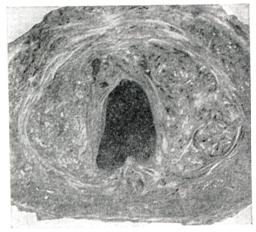

В предстательной железе в практическом отношении принято различать: верхнюю, или переднюю, — краниальную часть и нижнюю, или заднюю,— каудальную часть; с возрастом различие строения этих частей выявляется отчетливее (рис. 1 и 2).

Аденома развивается в краниальной части, а рак — в каудальной. Аденома и рак предстательной железы могут сосуществовать у одного и того же больного одновременно.

Предстательная железа при аденоме увеличена; вес ее может достигать 80—100 г и более. Микроскопически выделяют железистую, фиб-розно-мышечную и смешанную формы аденомы предстательной железы. Аденоматозные узлы построены из тесно расположенных ветвистых желез, образующих многочисленные крипты и сосочковые выросты. Железы выстланы 1—2 слоями клеток высокого призматического эпителия. В просвете желез — сгустившийся секрет, амилоидные тельца, скопления лейкоцитов. Строма узлов состоит из зрелой фиброзно-мышечной ткани, бедной клеточными элементами. Встречаются лейкоцитарные и лимфо-гистиоцитарные инфильтраты, абсцессы, очаги некроза.

При фиброаденоматозных структурах узлы состоят из редко разбросанных железистых элементов трубчато-альвеолярного строения. Строма узлов богата клетками типа фибробластов. Тубулярная аденома встречается редко. Узлы обычно единичные; они построены из извилистых или выпрямленных трубочек, выстланных одним рядом высоких призматических клеток с бледно окрашивающейся цитоплазмой и базально расположенными ядрами. Ядра гиперхромные без фигур деления.

Фиброзно-мышечные узлы, сфероиды, можно видеть почти во всех случаях наряду с узлами железистого строения. Эти узлы, как правило, множественные, редко превышают 1—2 сантиметра в диаметре. Они состоят из богатой клеточными элементами волокнистой ткани, напоминающей строму предстательной железы эмбриона; чаще в них преобладают клетки мышечного типа. В толще таких узлов можно видеть примитивно построенные трубочки, выстланные плоским, кубическим, реже однорядным высоким призматическим эпителием.